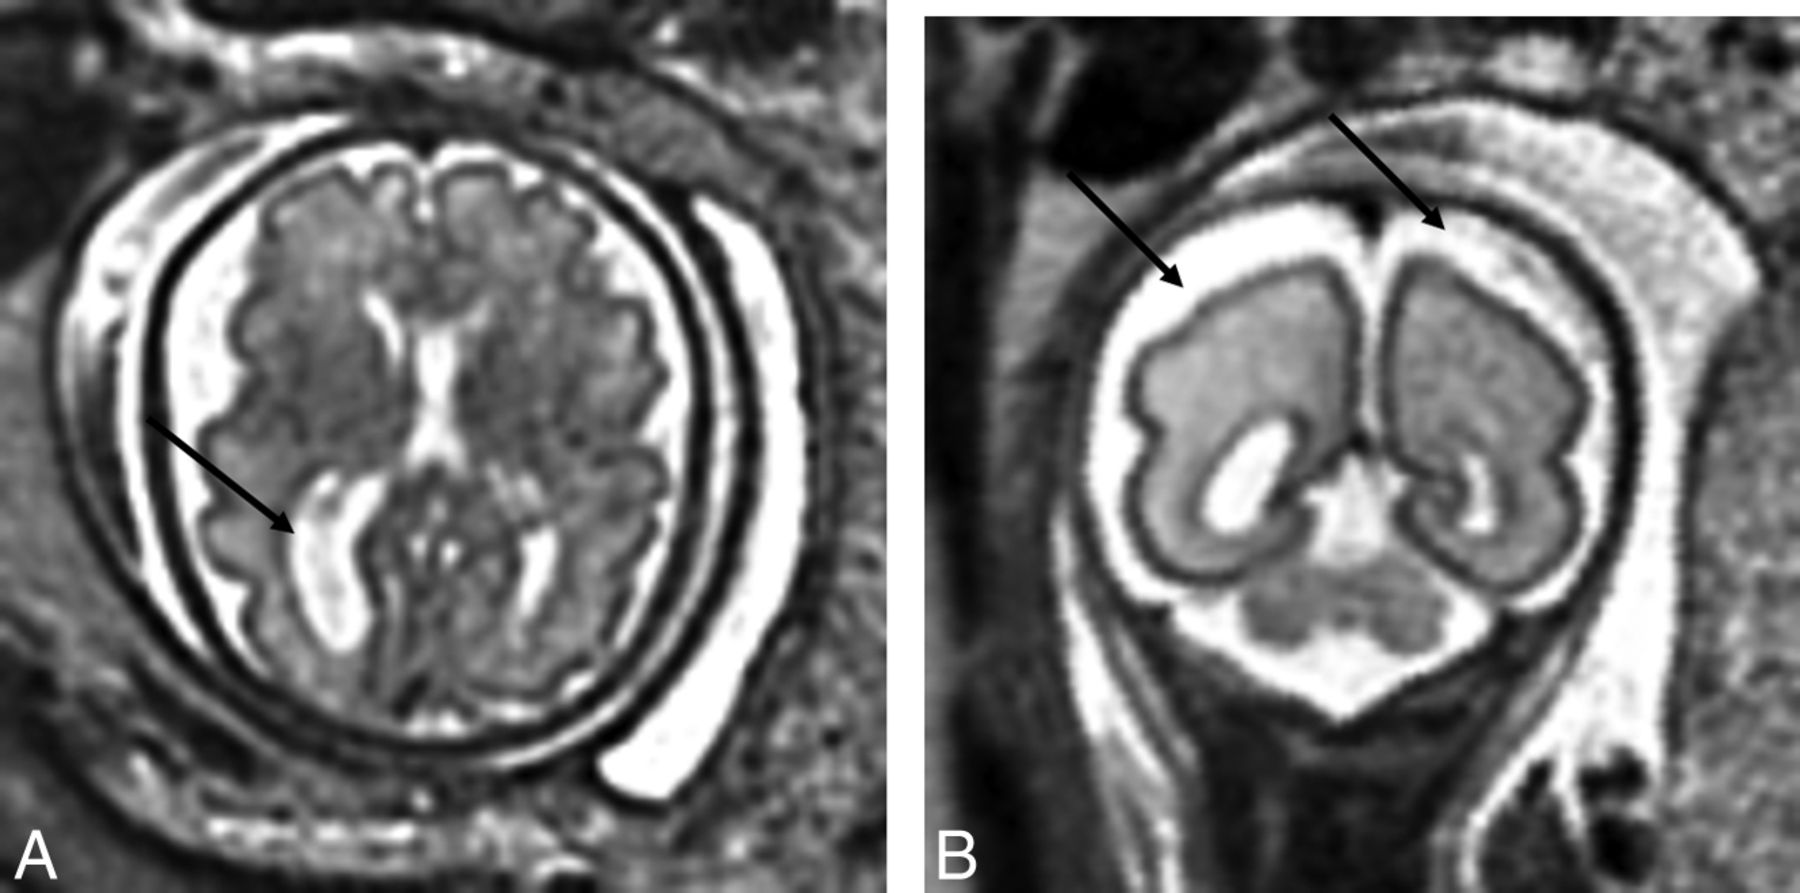

Thirty-two neonates (32.0%) had abnormal findings on conventional preoperative brain MR imaging. Acquired injury was present in 27 (26.2%) neonates. An isolated developmental anomaly (ie, without acquired injury) was detected in 5 neonates, while 5 others presented with both developmental and acquired findings. Hemorrhagic and nonhemorrhagic pWMIs were present in 15 neonates (5 mild, 10 moderate/severe), most commonly observed in the periventricular white matter, the centrum semiovale (Fig 2), and the frontal white matter. NHPI was the second most frequently acquired injury and was detected in 13 neonates. Of these, 7 presented with diffuse abnormal T2 signal prolongation (isolated in 2) in the periventricular white matter and 3 with focal infarctions in the deep gray matter (isolated in 1) (Fig 3). Three neonates presented with cysts: One had an isolated right germinal matrix cyst, 1 had a single cyst in the periventricular white matter, and 1 had multiple cysts in the bilateral frontal white matter.

T2-weighted axial view of a neonate with CHD with bilateral deep gray matter infarcts.

Nonparenchymal hemorrhages were reported in 11 neonates (isolated in 3 cases) and included the following: intraventricular hemorrhage in 1, GMH-IVH grade-I in 1, GMH-IVH grade-II in 5, GMH-IVH grade-III in 1, and choroid plexus hemorrhage in 3. Mild parenchymal hemorrhages were observed in 2 neonates, 1 in the cerebellum (Fig 4) and the other in the left globus pallidus.

T2-weighted coronal view of a neonate with CHD with unilateral cerebellar hemorrhage.